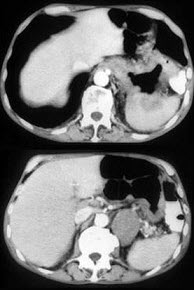

男,57岁,腹部隐痛不适伴低热2月余,腋下可触及数个肿大的淋巴结,请结合图像,作出诊断( )

A:左侧肾上腺癌并胃脾转移

B:左侧恶性嗜铬细胞瘤侵及胃脾

C:左侧肾上腺淋巴瘤且胃脾受累

D:左侧肾上腺腺瘤

E:左侧肾上腺转移瘤